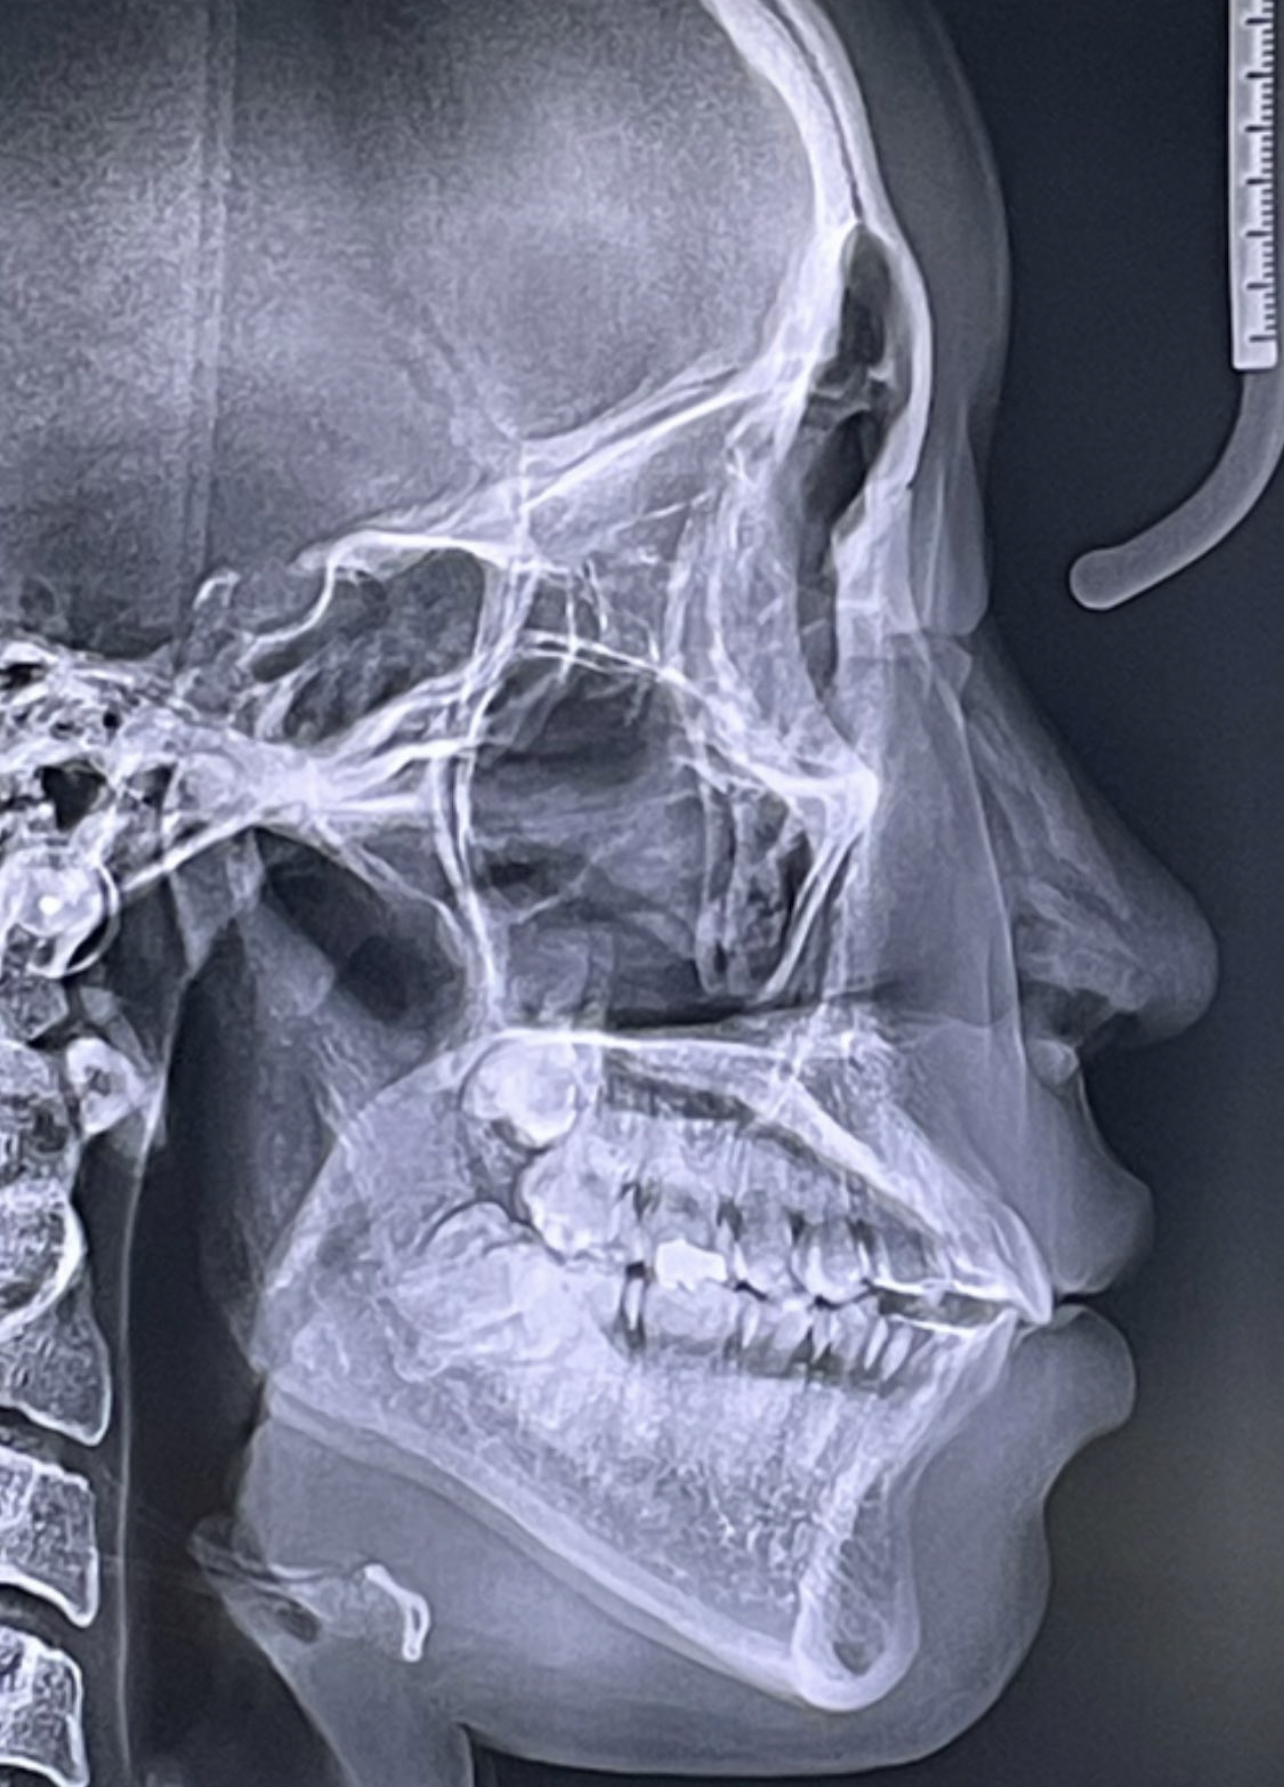

Recently got this implant design from Dr. Y for custom mandible (jaw & chin) and malar / cheekbones with infraorbital rims.

Also, noting my nose is actually incredibly swollen in the provided pictures & scan. Had rhinoplasty a few months back with Dr. Liotta in New York. She is excellent! Go-to for rhino imo.